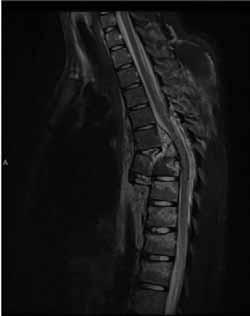

Rycina 70.5.

Rycina 70.6.

Rycina 70.7.

Rycina 70.8.